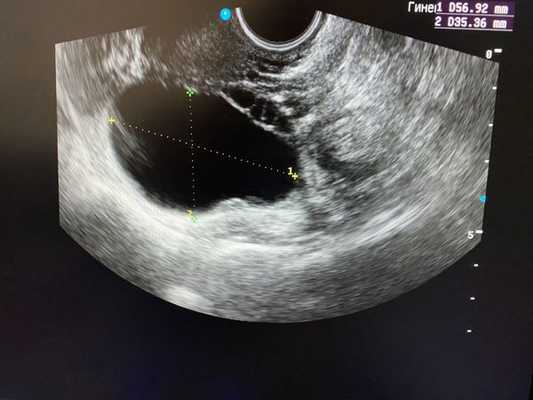

Как выглядят яичники при наличии кист:

Эхоскопически киста желтого тела определяется в виде анэхогенного однородного образования круглой формы от 4 до 8 см в диаметре, с ровными четкими контурами, иногда с мелкодисперсной взвесью внутри. Для точного распознавания лютеиновой кисты производится динамическое УЗИ в первую (фолликулярную) фазу менструального цикла. Проведение цветовой допплерографии (ЦДК) направлено на исключение васкуляризации внутренних структур кисты и дифференциацию ретенционного образования от истинных опухолей яичника.